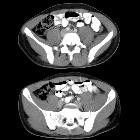

CT

- retroperitoneal structures have a hazy margin with fluid tracking through the retroperitoneum

- non-contrast

- acute and subacute hematomas - heterogeneous high attenuation

- chronic hematomas - low attenuation

- contrast-enhanced CT (without dedicated angiography)

- well-defined margin in case of a formed hematoma and absence of contrast enhancement